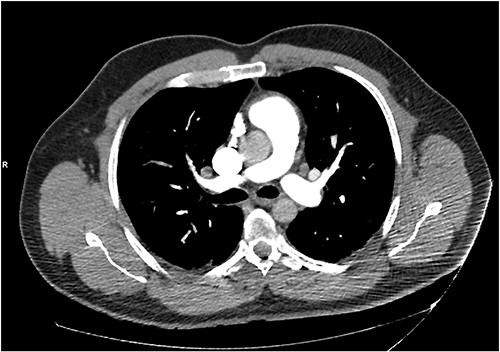

The patient was treated with IV piperacillin-tazobactam. However, he continued to have febrile temperature spikes. No growth was initially detected on blood cultures. The patient developed shortness of breath and respiratory alkalosis, for which a CT pulmonary angiography was done to exclude pulmonary embolism. Only dependent bilateral changes in the lower lobes and signs of mild pulmonary venous congestion were reported (Fig. 3). He was started on hydrocortisone, ethambutol, pyridoxine and rifampicin as empirical treatment for BCGosis. Hydrocortisone was eventually tailored down to prednisolone. Virology tests including hepatitis and immunodeficiency virus were run and these were negative. He continued spiking high temperatures and a repeat CT abdomen with IV contrast was performed which was largely unchanged from the previous scan (Fig. 4). An echocardiogram ruled out infective endocarditis. Incidentally he was in contact with a COVID-19 positive patient and was placed under quarantine for 14 days. Fortunately, he never developed COVID-19 infection. Another CT pulmonary angiography was performed in view of persisting shortness of breath but only mosaic attenuation in the lungs was present.

A CT pulmonary angiography was done to exclude pulmonary embolism. Only dependent bilateral changes in the lower lobes and signs of mild pulmonary venous congestion were noted.